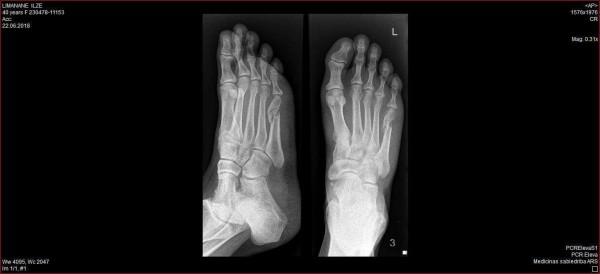

Esam ar Inu ceļā uz Rīgu, kad vīrs man uzraksta laba starta vēlējumus. Tad gan saprotu, ka ir jāatzīstas. Nosūtu bildi ar savu zili sapampušo kāju un tekstu, ka paskaidrojumi būs vēlāk, bet šobrīd man ir nepieciešams nokļūt no Riga Plaza, kur Ina mani laipni izsēdina, uz ARS. Izrādās – es pati nemaz neprotu izsaukt taksi, nu vismaz ne šādās situācijās. Vīrs to izdara manā vietā, taksists gan ir visai apmulsis vīrieša vietā ieraugot lēkājošu blondīni ar basu kāju, bet tas tomēr neattur viņu nogādāt šo “nelaimes putnu” ARS. Ielēkšoju traumu kabinetā, un daktere, uzmetot paviršu skatienu, paziņo – lauzts! Jūs jokojat???!!! Nevar būt lauzts, es taču nodejoju deju līdz galam, nogāju vienu kilometru līdz viesnīcai, nomocīju nakti, man nav nenormālu sāpju un, ja būtu lauzts, tad es noteikti zinātu! Daktere laikam šādus pacientus ir atklausījusies un bez ceremonijām mani nosūta uz rentgenu, bet māsiņai liek gatavot ģipsi. Ieejot kabinetā pēc rentgena, dakteres monitorā es redzu savus pēdas kauliņus, tur pat ārsta izglītību nevajag, lai redzētu, ka ir 100% lauzts! Izplūstu asarās un saku, ka man pēc nedēļas jāskrien Vilkaču maratons. Nebūs, viņa saka, bet labāk būtu klusējusi. Šogad nebūs! Viņa izraksta man cedelīti uz operāciju un silti iesaka to veikt līdz Līgo svētku traumas nogāžas pār Duntes ielas traumpunktu. Bāc, kādu vēl operāciju… Tomēr izrādās – lūzums ir visai sarežģīts, un atdalīti kauli savā starpā nesaug, nepieciešams tos savilkt kopā. Nopērku kruķus un visai šokēta sēžu ARS koridorā ar skaistu, baltu langeti uz kājas. Es brīdi apmulstu un nesaprotu, kas tagad ir jādara. Ir skaidrs, ka nepieciešama operācija. Laikam jābrauc uz Duntes ielu, bet, kā tas viss galu galā notiks, man īsti skaidrs nav. Metu kaunu pie malas un piezvanu savai kolēģei, kuras vīrs ir ārsts. Paralēli, pateicoties Alīnas superspējām, no mana rentgena CD diska tiek izvilinātas bildes, kas der nosūtīšanai telefonam saprotamā formātā. Tikmēr arī mani vīrieši ir tikuši prom no darbiem un ir gatavi mani aizvizināt uz jebkuru slimnīcu Rīgā. Tomēr viņu sejās redzams manāms neslēpts šoks. Mašīnā, kamēr sēžam un gaidām ārsta rīkojumus, ko darīt tālāk, valda neveikls klusums. Mani nav piemeklējusi baisa slimība, man nav liegta spēja kustēties, bet tomēr ir skaidrs, ka šis notikums mainīs mūsu vasaras plānus visai nopietni.

Pirmais rentgens